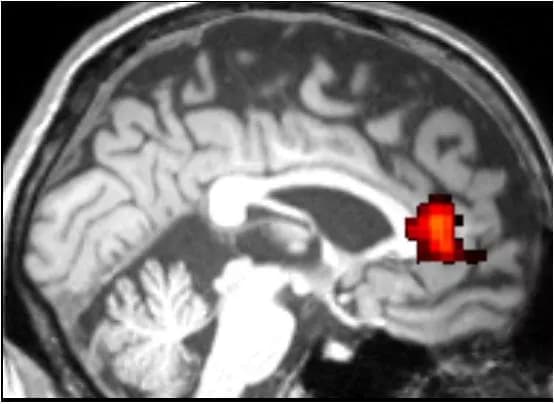

Published Nov. 17 in the journal AIDS Care, functional MRI (fMRI) scans, taken while participants were performing an alternating face-gender/word-semantic task, revealed that HIV+ individuals in the study showed deficits in cognitive functioning, compared to an age matched healthy controls.

The HIV+ group was significantly slower in adjusting to change in tasks, which correlates with brain dysfunctions in the dorsal anterior cingulate cortex (dACC), one of the key executive regions. This collar-shaped area is near the front of the brain, and damage to this region has been linked to many cognitive impairments, including executive deficits and apathy.

"Intriguingly, both impairments are highly prevalent in individuals with HIV-infection, suggesting dACC might be one of commonly affected brain regions in HIV and a potential neural target for therapies," says Jiang.